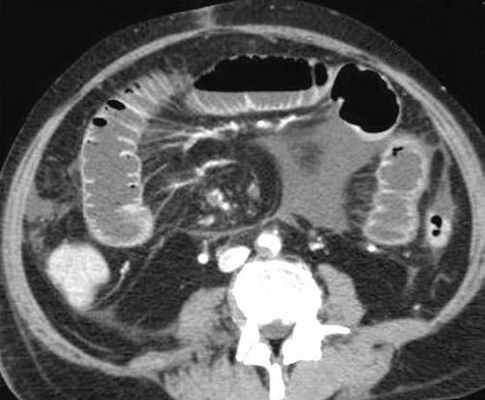

КТ визуализация при простой форме

Хирургическая классификация тонкокишечной непроходимости также является основой классификации, используемой в радиологии. Раличают три формы:

- простая/компенсированная форма

- декомпенсированная форма

- осложнённая форма.

-Расширенные петли тонкой кишки проксимальнее транзиторной зоны (зоны обструкции).

-Под транзиторной зоной надо понимать зонy кишки с очевидной разностью в диаметре просвета между расширенным проксимальным сегментом и местом сужения/обструкции. Визуализация этой зоны зависит от причины и механизма обструкции, а также от проекции расположения петли (аксиально, фронтально и т.д.). К сожалению, обнаружение этой зоны не всегда представляется возможным. При спаечном механизме или воспалении многими хорошо описан признак "птичьего клюва". При обструкции в результате алиментарного болюса транзиторная зона будет выглядеть как гетерогенное образование в просвете кишки без признаков контрастного усиления.

-Спавшиеся петли кишечника дистальнее уровня обструкции.

-Смешанный характер стаза содержимого кишечника в расширенных петлях. Некоторыми авторами описан "фекалоидный" тип стаза, описанный в литературе как "каловое содержимое тонкой кишки", в английской литературе-“small-bowel faeces sign”. Патогенез данного признака включает в себя много факторов:

замедление пассажа содержимого, нарушения механизмов абсорбции и секреции в тонкой кишке, рефлюкс из толстой кишки из-за недостаточности илео-цекального клапана, постановка желудочного зонда. Необходимо помнить, что этот признак неспецифичен при тонкокишечной непроходимости, его также можно определить на УЗИ и обзорной рентгенограмме брюшной полости.

-Нормальные неутолщённые стенки кишечника с гомогенным одинаковым контрастным усилением.

-В тощей кишке рисунок ворсинок слизистой (valvulae conniventes) тонкий, и он одинаково выглядят на всём протяжении.

-Отсутствие патологических изменений толстой кишки, толстая кишка как правило спавшаяся или содержит небольшое количество калового содержимого, распределённого по всему просвету.

-Отсутствие воспалительных изменений в брыжейке и внутрибрюшинном жире.

-Нормальная васкуляризация сосудов брыжейки.

-Отсутствие свободной жидкости в брюшной полости.

Различные КТ сканы при простой форме обструкции, cxематично изображены транзиторные зоны и спайки, которые как "хомут" или "удавка" как-бы душат петлю кишки.